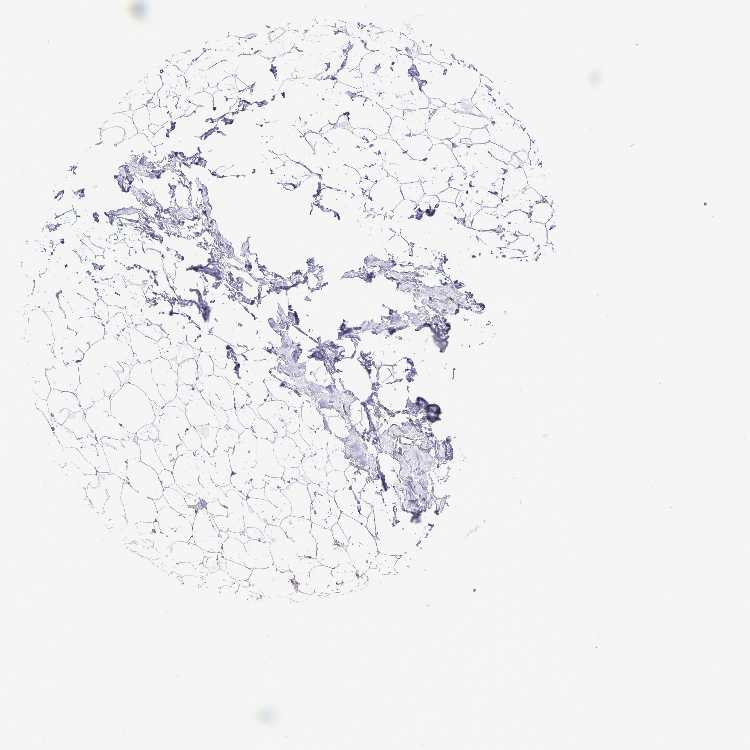

BREAST - Antibody stainingi

Antibody staining in the annotated cell types in the current human tissue is reported as not detected, low, medium, or high, based on conventional immunohistochemistry profiling in selected tissues. This score is based on the combination of the staining intensity and fraction of stained cells.

Each image is clickable and will lead to virtual microscopy that enables deeper exploration of all samples and also displays staining intensity scores, fraction scores and subcellular localization as well as patient and tissue information for each sample.

Antibody HPA062724Antibody HPA063392

Adipocytes Not detectedNot detected

Glandular cells Not detectedLow

Myoepithelial cells MediumNot detected